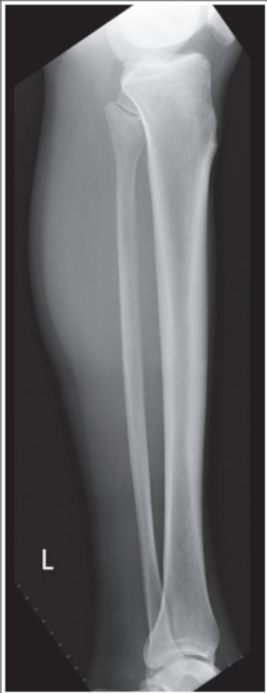

Proximal tib/fib are not superimposed

Over superimposition of tib/fib

Superimposition of proximal tib/fib

Obliquity is less than 45 degrees, meaning its under-rotated